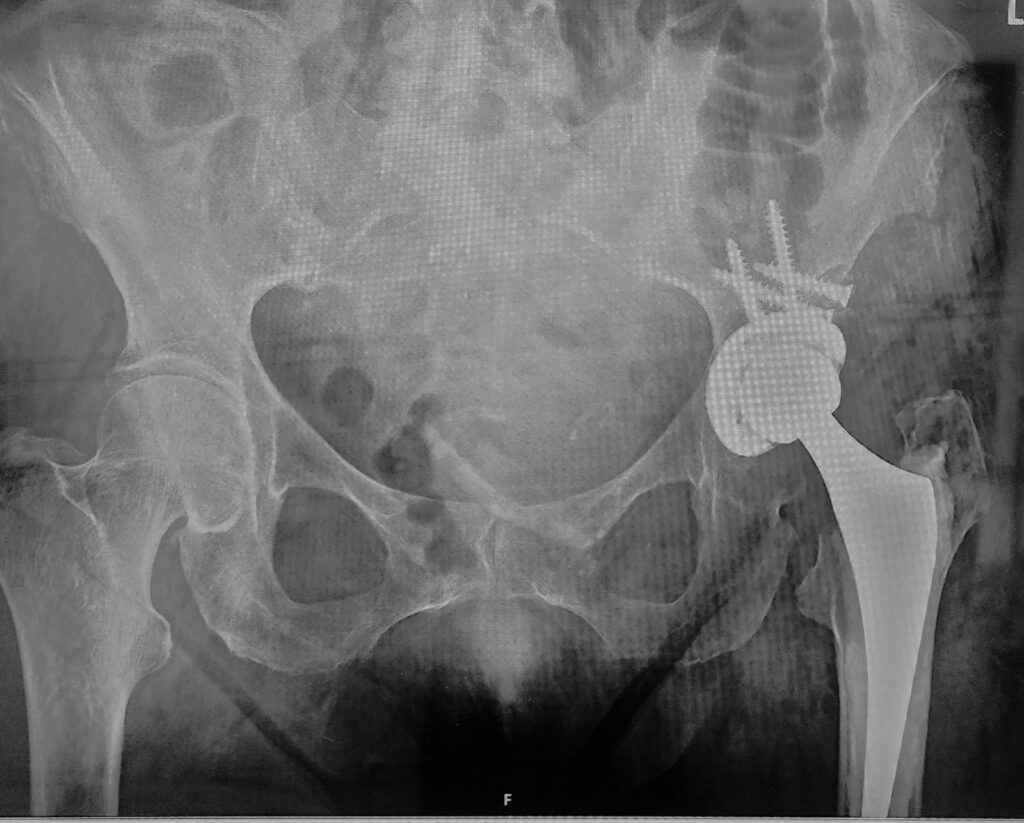

The post-operative X-rays show:

- A well-positioned hip prosthesis

- Reconstructed acetabulum with bone grafting

- Restored joint alignment and leg length